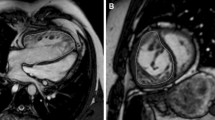

Measurements of intra- and inter-ventricular dyssynchrony

For the assessment of intra- and inter-ventricular dyssynchrony (Fig. 1), both systemic RV and pulmonary LV in the short-axis, and four-chamber cine images were assessed using a feature-tracking method Vitrea (Canon Medical Systems Corporation, Otawara, Japan). The systemic RV in the short-axis of the mid-ventricular level, and at the four-chamber view, was divided into six segments. The intraventricular dyssynchrony time was defined as the maximum difference between the peak times of septum and systemic RV free walls. The interventricular dyssynchrony time was defined as the maximum difference between the peak times of the biventricular free walls.

Feature tracking on CMR. Intraventricular dyssynchrony: systemic RV at the four-chamber was divided into 6 segments. The intra-ventricular dyssynchrony time was defined as the difference between the peak times of septum and systemic RV free wall. White line showed longitudinal global strain. Interventricular dyssynchrony: both RV and LV were considered as a single heart and the interventricular dyssynchrony time was defined as a difference between the peak times of biventricular free walls